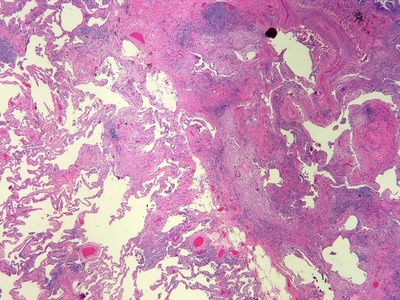

Interstitial inflammation

Inflammation focused in tissue interstitium rather than surfaces, often in lung or kidney. Causes organ-specific symptoms like breathlessness in interstitial pneumonitis or impaired kidney function; specialist care often required.

Pneumonitis/interstitial pneumonitis

Inflammation of lung interstitium causing cough and progressive breathlessness. Causes include infections, drugs, or hypersensitivity. Can lead to scarring and respiratory failure; urgent care for worsening breathlessness.